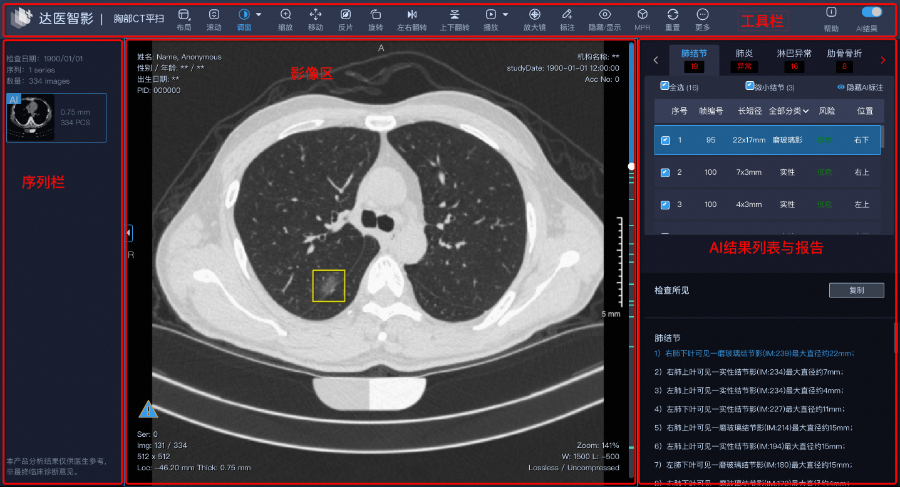

据悉,项目依托阿里巴巴达摩院医疗AI实验室自研的智能读片产品“达医智影”。通过常规胸部、腹部CT平扫,以“平扫CT+AI”方式帮助诊疗,胰腺癌、肝癌、食管癌、胃癌、结肠癌等占据新发癌量38.1%的病灶发现,辅助医生对骨质疏松、脂肪肝及肺结节等总计13个病种进行疾病筛查、诊断、治疗和随访全流程,提高临床诊断准确率和效率。

达医智影可以辅助医生进行疾病筛查、诊断

影像学手段与AI人工智能相结合的癌症筛查手段,既有CT检查的高普及度,又兼顾人工智能的高灵敏度,可以在患者的日常体检与医院检查“z4”中进行癌症筛查。